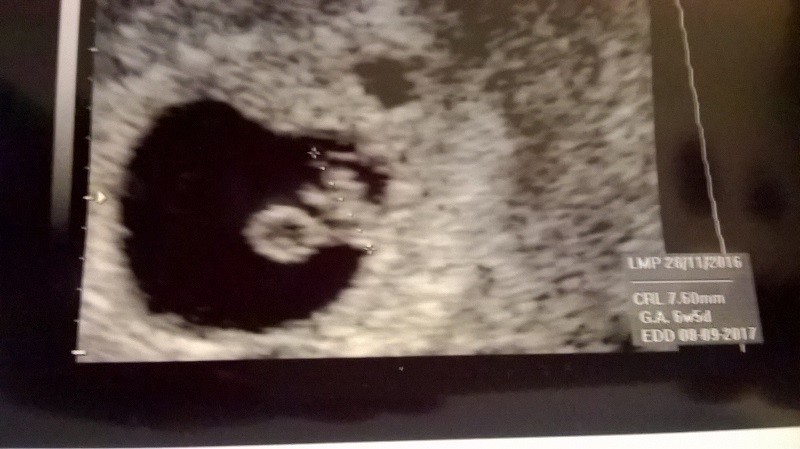

No i tak trzymaj, po co się niepotrzebnie stresować? Od razu masz obniżony nastrój przez to, organizm inaczej pracuje. Nie ma co robić wcześniej :-)Następnym razem to kupię test grubo po terminie @a nie wiecznie oglądanie jednej kreski